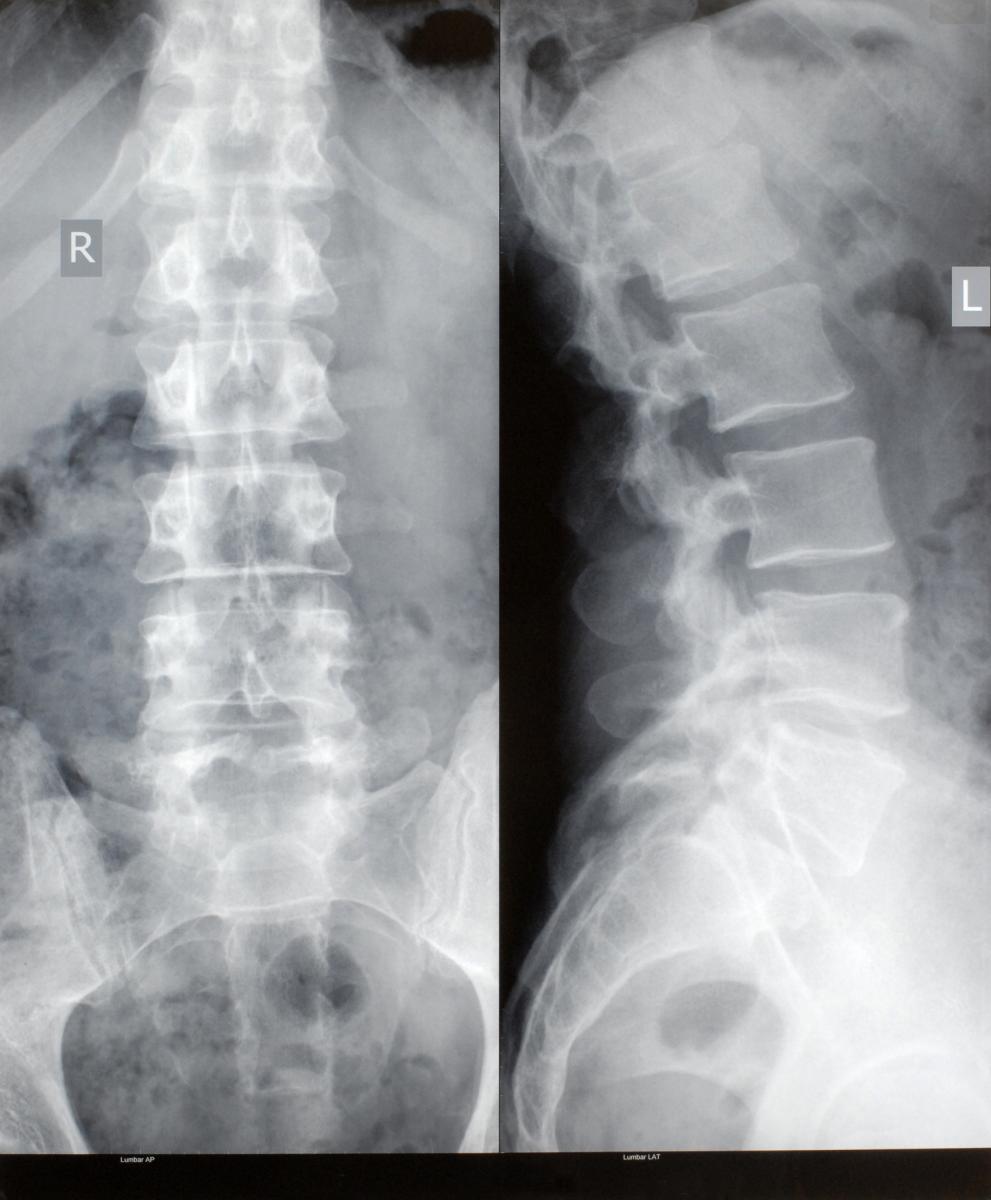

Los Rayos “X” de columna lumbosacra AP y lateral

Se lleva a cabo a través de una radiografía de los pequeños huesos (vértebras) en la parte baja de la columna (región lumbar) y el sacro, el área que conecta la columna a la pelvis.

La radiografía de la columna lumbosacra ayuda a evaluar las lesiones en la espalda, así como entumecimiento, lumbago o debilidad persistentes. Se detectan anomalías tales como fracturas, dislocaciones, osteoporosis y deformidades en la curvatura de la columna; al igual que espolones óseos, problemas de discos tales como hernia discal, y degeneración de las vértebras.